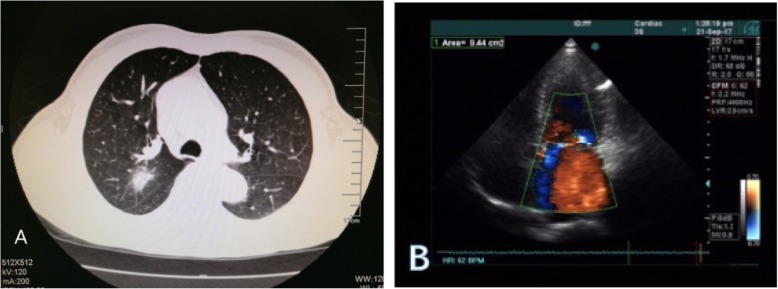

A 67-year-old man identified an enlarging heterogeneous mass in the posterior segment of his right up lobe. The patient had symptoms of shortness of breath after activity and physical examination revealed a grade 3–4 of 6 holosystolic murmur. Echography of the abdomen, Computed tomography (CT) scan of the brain, bone scintigraphy and Positron Emission Tomography (PET) were performed to define the pulmonary malignancy and excluded distal metastases (Fig. 1a), tumor was classified and staged T2N0M0. An electrocardiogram (ECG) revealed examination demonstrated severe prolapse of the posterior mitral leaflet with flail of the middle scallop (P2, P3 segment) (Fig. 1b), the left atrial (LA) and left ventricle (LV) was extensive (LA 46 mm, LV 55 mm), the patient was severe mitral regurgitation with New York Heart Association (NYHA) class II. Lung function tests and coronary angiography were unremarkable. The patient denied family history of related diseases. Patient elected the option of a one-stage ipsilateral VATS and minimally invasive cardiac surgery as definitive diagnostic and therapeutic procedures.

Fig. 1.

a Computed tomography imaging scans identified a right upper lobe apical mass. b Transthoracic echocardiographic imaging of Mitral prolapse associated with severe MR